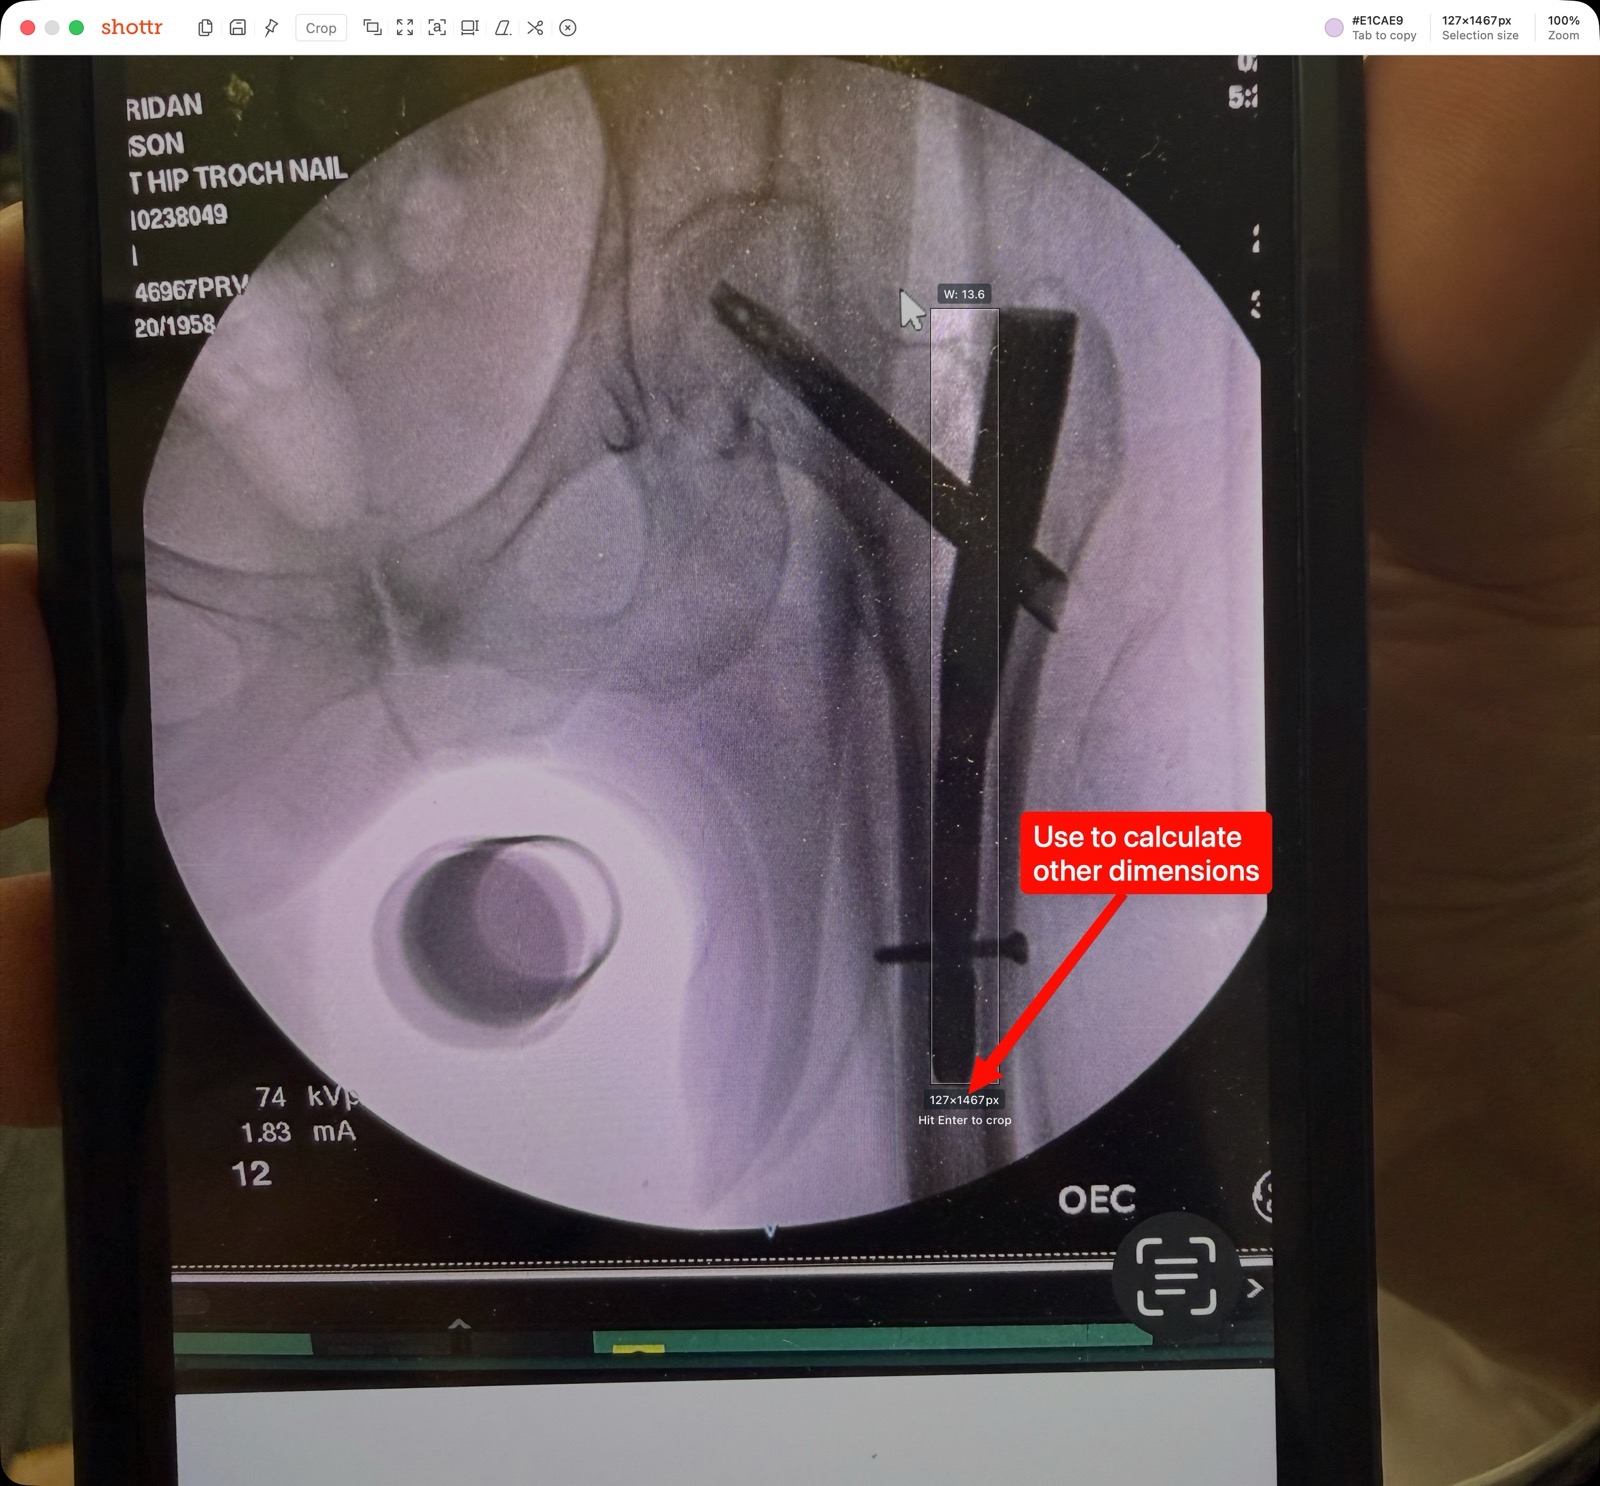

I used my favorite screenshot utility, Shottr, to measure the length of the rod in pixels in the photograph I had from the doctor of my X-ray. From that, knowing the length and the number of pixels, I could get an inches-per-pixel multiplier that I could use to figure out the true diameter of the screws and the rod.

But then I got curious about whether there were maybe standard pieces of hardware for this kind of surgery. I noticed in the X-ray it said “hip troch nail”, so I asked Perplexity to give me some information on the exact hardware that might have been used for this kind of surgery.